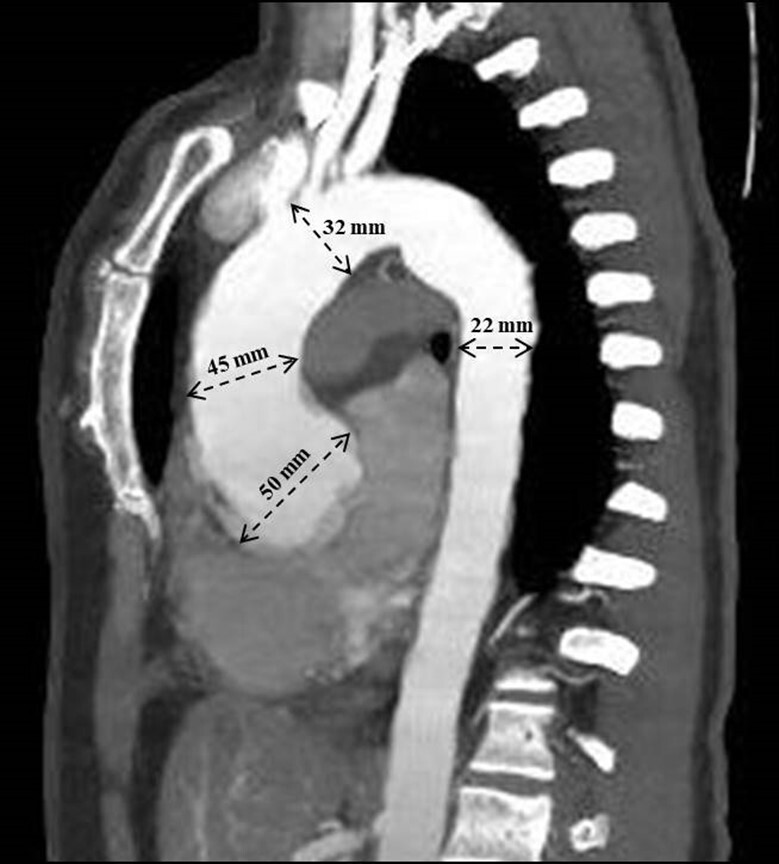

巨细胞动脉炎(GCA)是一种影响中、大口径动脉的慢性血管炎,通常与主动脉受累有关,从而导致动脉瘤形成。然而,伴有巨细胞性瓣膜炎并不常见。我们报告一例50岁的女性主动脉瘤和瓣膜功能不全的病例,其解剖病理检查显示巨细胞性主动脉瓣膜炎与巨细胞性大动脉炎相关。

Giant cell arteritis (GCA) is a type of chronic vasculitis that affects medium and large-caliber arteries, frequently related to aortic involvement and, consequently, to aneurysm formation. However, associated valvulitis with giant cells is uncommon. We describe the case of a 50-year-old female patient with aortic aneurysm and valvular insufficiency, whose anatomopathological examination revealed giant-cell aortic valvulitis associated with giant cell aortitis.